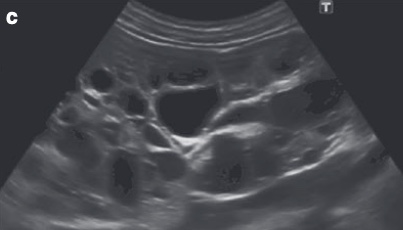

MuliCystic Dysplastic Kidney Disease

General

- Rein non fonctionel, multikystique unilatéral

- Rein gauche > Droit

- Jamais bilatéral car non compatible avec la vie

- Rein controlatéral avec anomalies (reflux, syndrome de la jonction,…)

- Seconde masse abdominale du nouveau né après Syndrome de la jonction

- Pas beson de néphrectomie, pas de risque de transformation maligne

US

- Contrairement au Syndrome de la jonction, le plus gros kyste est excentré